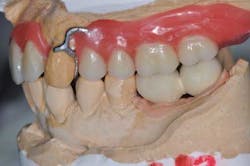

Figs. 5a and b: Impression for the RPD framework including the PFM frameworks and mounting